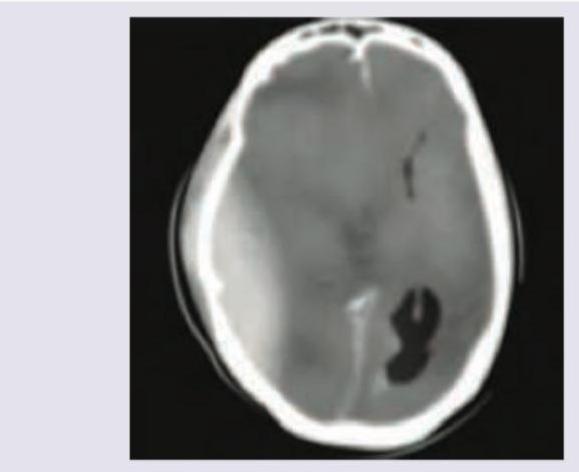

A 25-year-old patient presents in coma with GCS of 5 and extensor posturing after a bike accident. CT head was performed. Which of the following will be the best management of the patient?

Explanation: ***Burr hole surgery*** - The CT scan shows a large **epidural hematoma (EDH)**, which is a neurosurgical emergency requiring rapid evacuation to relieve pressure on the brain. - A GCS of 5 with extensor posturing indicates severe neurological compromise with **brainstem compression** and critically elevated **intracranial pressure (ICP)**, requiring immediate surgical decompression. - Surgical indications for EDH include: **hematoma volume >30 mL**, **midline shift >5 mm**, or any EDH with neurological deterioration regardless of size. - Burr hole craniotomy or formal craniotomy is the definitive treatment, with choice depending on size and accessibility of the hematoma. *Hypertonic saline* - This medication is used to acutely reduce **intracranial pressure** by creating an osmotic gradient that draws fluid out of brain tissue. - It serves only as a **temporizing measure** during preparation for surgery or transport, not as definitive treatment for a large EDH requiring evacuation. - Medical management alone would be fatal in this scenario with such severe neurological compromise. *Thrombolysis* - **Thrombolysis** is used to dissolve blood clots in conditions like acute ischemic stroke or pulmonary embolism where the clot is causing vascular obstruction. - It is **absolutely contraindicated** in cases of intracranial hemorrhage or recent head trauma, as it would exacerbate bleeding and worsen outcome. - Using thrombolysis in this patient would likely be fatal. *Ventriculoperitoneal shunting* - This procedure is used to treat **chronic hydrocephalus** by diverting excess cerebrospinal fluid (CSF) from the brain ventricles to the peritoneal cavity for absorption. - While traumatic hydrocephalus can occur, it develops weeks after injury, not acutely. - The immediate life-threatening issue is the **space-occupying hematoma** causing mass effect and herniation, not CSF accumulation.